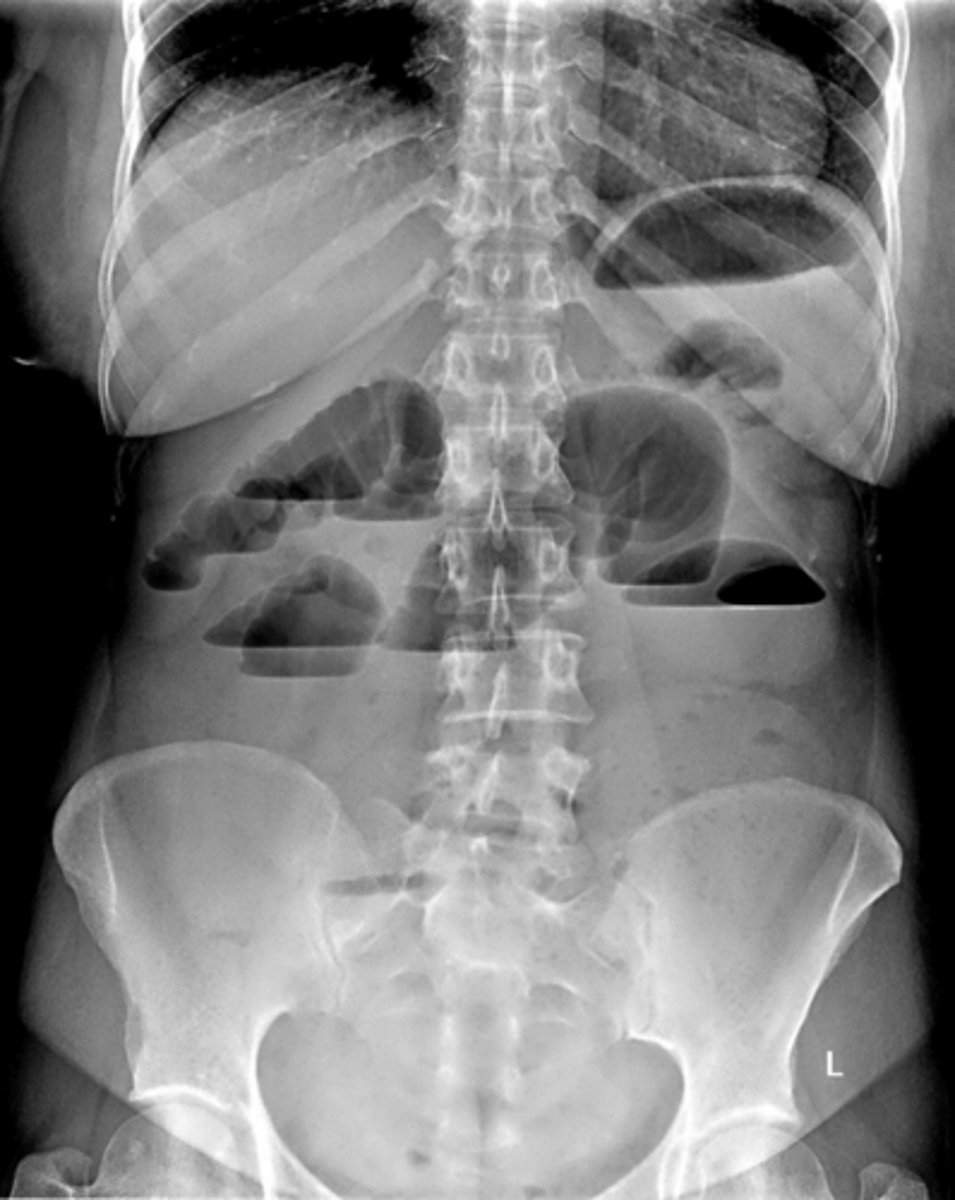

Air fluid levels due to small bowel obstruction (SBO)

____ bowel has 2-3 air/fluid levels present normally in upright/lateral decubitus view. _____ bowel has no or a few air/fluid levels present on upright XR

small, large

air fluid levels

caused by intestinal obstruction, prevents flow of fluids and gas, appears like a turtle shell